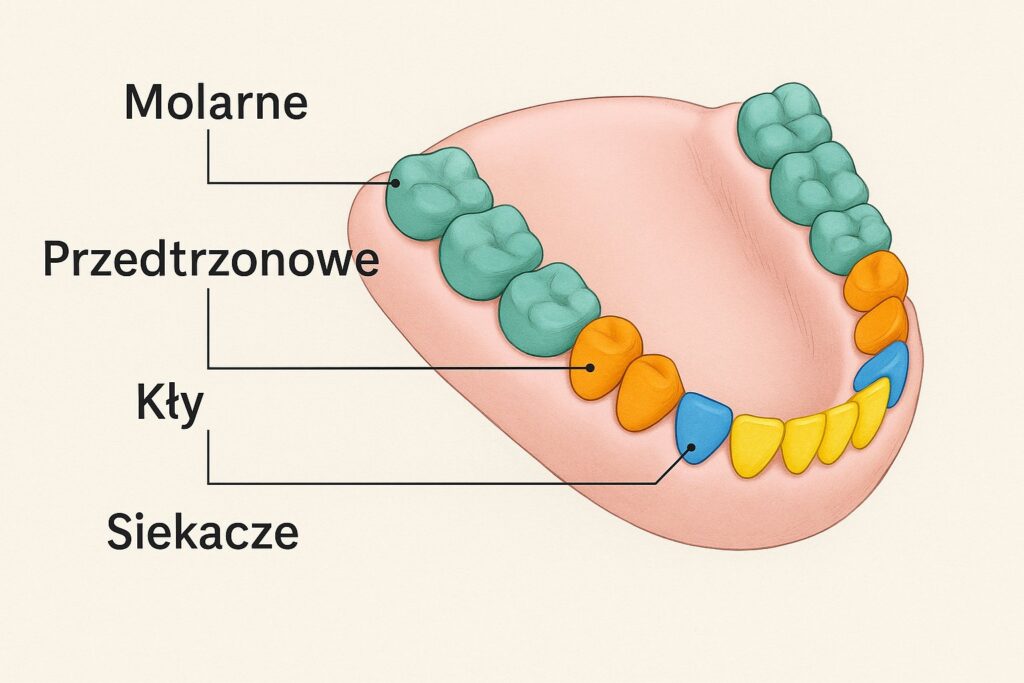

W takich przypadkach pojawia się stały, tępy ból o różnym nasileniu. Przy nacisku na chory ząb ból się nasila i może promieniować do sąsiednich zębów wzdłuż nerwu trójdzielnego. Stopniowo dziąsło wokół objętego zapaleniem miejsca czerwienieje i puchnie, a w ustach pojawia się ostry, nieprzyjemny zapach. Na języku tworzy się nalot, a ślina staje się gęsta i lepka.

Gdy infekcja wnika głębiej, stan zapalny zaczyna się rozprzestrzeniać. Powoduje to stwardnienie tkanek oraz obrzęk twarzy i szyi. Ból, który początkowo ma charakter miejscowy i tępy, staje się pulsujący i bardziej rozległy – wychodzi poza obręb szczęki. Pacjent ma trudności z żuciem i pełnym otwarciem ust, pojawia się ból przy nagryzaniu, zęby mogą się chwiać, a węzły chłonne w zajętym obszarze powiększają się i stają się bolesne.